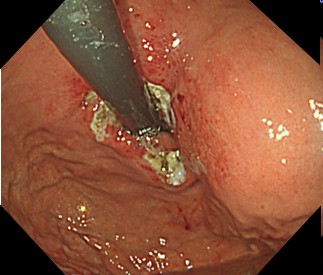

内視鏡で胃と食道のつなぎ目の粘膜を切除して、修復過程で狭くなることを利用して、逆流を防止します。